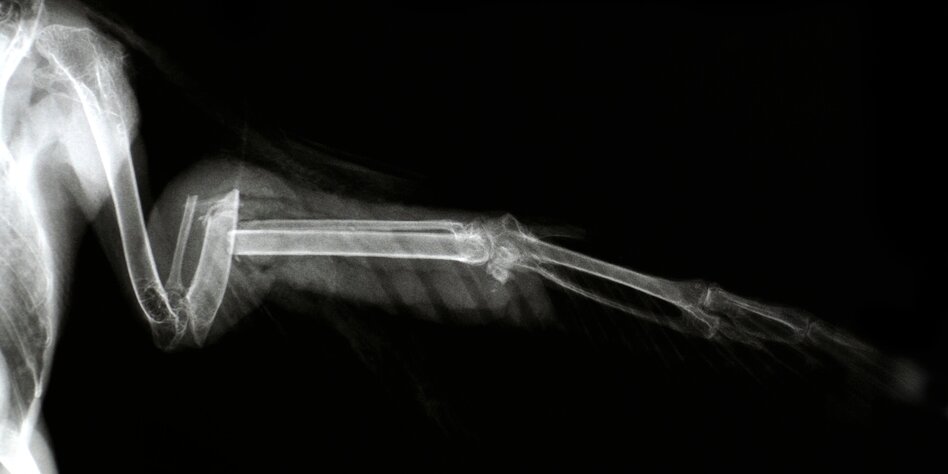

(IMG) Bild: Vögeln den gebrochenen Flügel verarzten? So romantisch ist es meist nicht

Einen Vogel mit gebrochenem Flügel verarzten, bei der Geburt von Kälbchen

helfen und täglich zig Hunde und Katzen streicheln – so vielleicht stellen